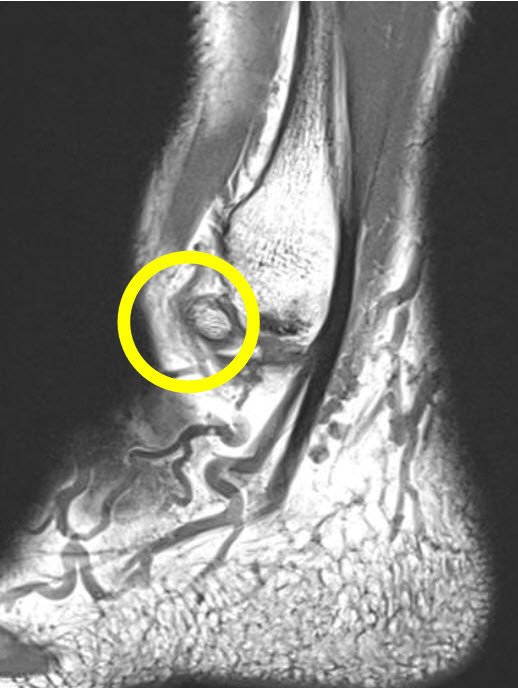

Bei der daraufhin veranlassten MRI-Untersuchung kann ein Zusatzknochen oder auch akzessorischer Knochen vor dem Aussenknöchel nachgewiesen werden (Abb. 1). Aufgrund seiner Lokalisation handelt es sich um ein Os subfibulare. Es muss davon ausgegangen werden, dass die Verbindung dieses Knochens zum Aussenknöchel durch den Unfall gelockert wurde. Die daraufhin immer wieder auftretenden Reibungen zwischen den Knochenflächen sind schmerzhaft.